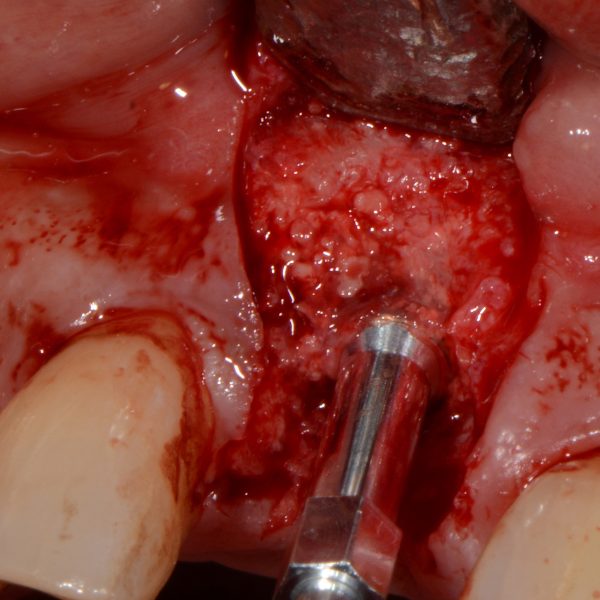

Resorbable Suture Tenting

Pain from a mobile upper right central incisor that had received trauma approximately ten years prior to presentation.